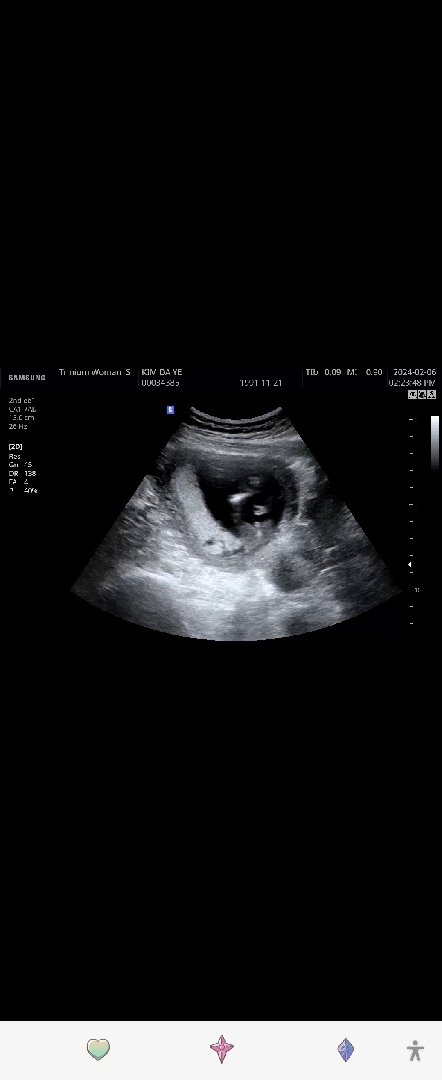

15주차 초음파보고왔는데 저게 고추일까요?

애기가 다리를 꼬고있어서 아쉽지만 성별확인 못하고왔어요ㅜㅜ제가 집에와서 유심히 보면서 캡처한건데요 애기가 발로 차는 모습인데 저게 탯줄인지 고추인지 모르겠어요 잘보시는분들 부탁드려요!